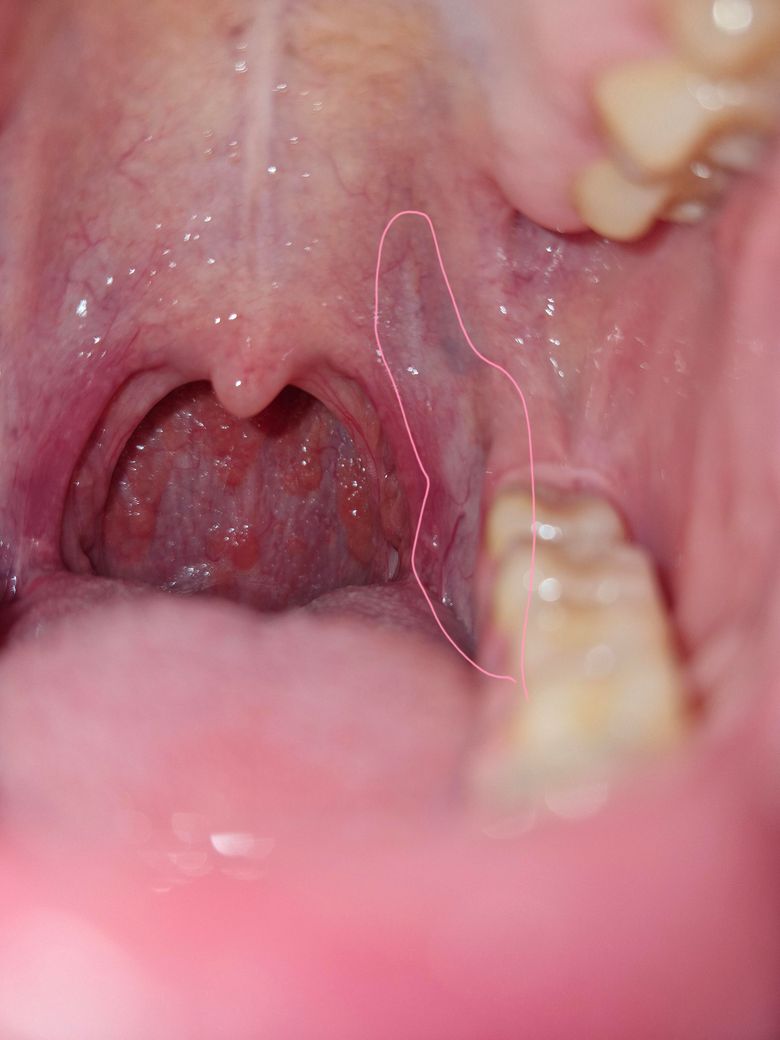

입안 백반증인가요? 한번봐주세요 ㅠ

생긴지는 꽤 됐는데 그냥 다들 그런가보다 하고 살았는데, 급 걱정이 돼서요. 근데 몇개월째 인후통이 간간히 있고 혀 안쪽이 아파서요... 입이 전체적으로 빨간기가 있습니다 ㅠㅠ넘 걱정돼요

사진상에 보이는건 백반증은 아니고 오히려 인후통은 편도에 문제 때문에 생긴거 같습니다.

백반증으로 보이지는 않으나 구내염으로 보입니다. 우선 소독용 헥사메딘 가글액으로 가글하여 관리하여 주길 권하며, 빨간기와 통증, 그리고 몇 달 이상 지속되는 인후통은 자세한 검사가 필요로 됩니다.